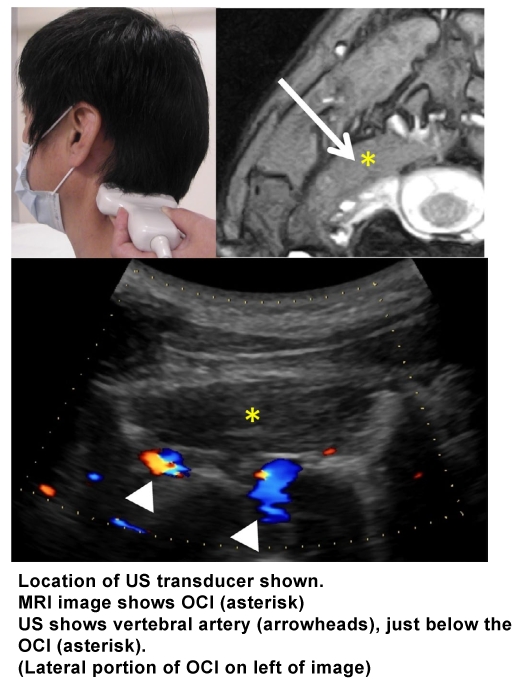

1. Place the convex transducer horizontally on the posterolateral neck at a level just below the tip of the mastoid process.

2. Rotate the dorsal end of the transducer a little downward, and turn the transducer a little in a rostral direction.

3. Identify the OCI. Normally, it is sausageâ€like, but may become ovoid in shape when it is hyperactive. The vertebral artery is just beneath the muscle. Confirm it with the color Doppler imaging. When the OCI is difficult to detect, because of intramuscular fibrosis the vertebral artery may help identify the muscle. There are occasionally other arteries superficial to the OCI.

4. Measure the approximate depth from the skin to the OCI and the muscle thickness before needle insertion in order to penetrate the muscle and not injure the vertebral artery.

6. After confirming the absence of any major artery along the expected needle path, insert the needle (27 gauge, 38 mm) from above the transducer. Direct the needle tip slightly downward so as to let the needle proceed within the ultrasound coverage area. Botulinum toxin is usually injected into medial and lateral portions of the muscle, but if the muscle is shortened by contraction its central portion may be the only site of injection.